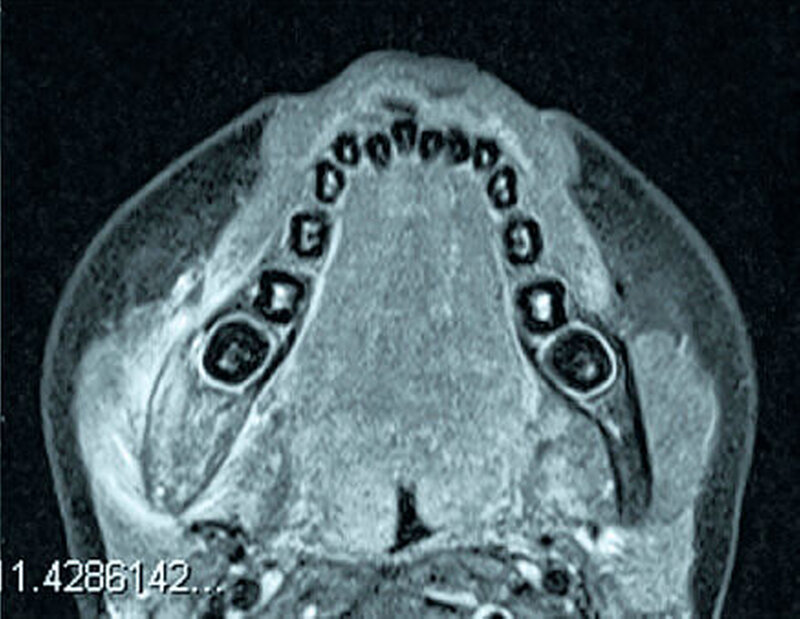

Die Magnetresonanztomografie (MRT) als röntgenstrahlenfreies Schnittbildverfahren mit hohem Weichteilkontrast erlaubt eine sehr gute Beurteilung des Knochenmarks und der Weichteile (Abbildung 4). Morphologische Sequenzen zeigen ein Knochenmarködem im Rahmen einer Entzündung sensitiv an, sind jedoch wie die Skelett- szintigrafie nicht spezifisch. Die MRT bietet im Vergleich zur Szintigrafie einen signifikanten Vorteil in Detektion und Ausbreitungserfassung der extraossären Entzündungsausdehnung [Reinert et al., 1999]. Eine Limitation der MRT stellte bislang die nur eingeschränkte Darstellungsmöglichkeit von Knochendestruktion und von Sequestern dar [Stockmann et al., 2010]. Neue Sequenztechniken wie zum Beispiel UTE-Sequenzen („ultrashort echo time“), die in den vergangenen Jahren für die Darstellung der Knochenstruktur entwickelt wurden, könnten diesen Nachteil künftig überwinden [Du et al., 2013].